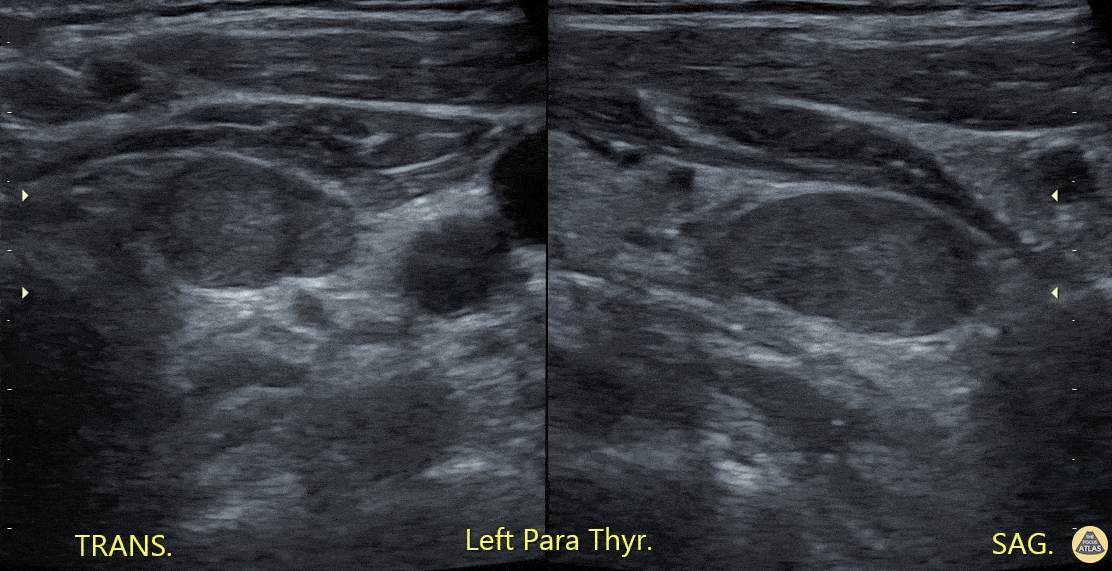

Soft Tissue - Parathyroid Mass

A patient with clinical and laboratory evidence of hyperparathyroid function underwent POCUS of thyroid/parathyroid region. Seen here is a slightly hypoechoic rounded, vascular structure (imaged in both transverse and saggital planes) felt to represent the culprit lesion. Abdulmajid Mubarak, @mjed136